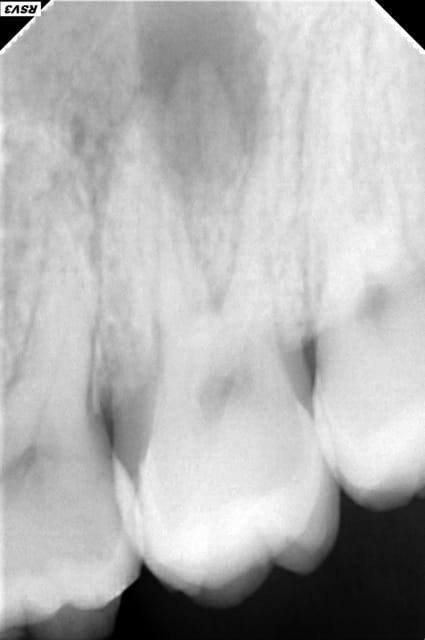

Patiente 18 ans, se présente pour douleurs à la pression dans le secteur 2.

Examen clinique: Fistule palatine et voussure vestibulaire en regard de 27.

Douleur percussion 27.

La dent est indemne. Pas de carie.

La radio parle d'elle même.

C'est bien une nécrose pulpaire qui s'est compliqué en abcès apical? C'est possible sur une 7 une nécrose spontanée comme ça (j'entend par la un choc antérieur ou autre...)